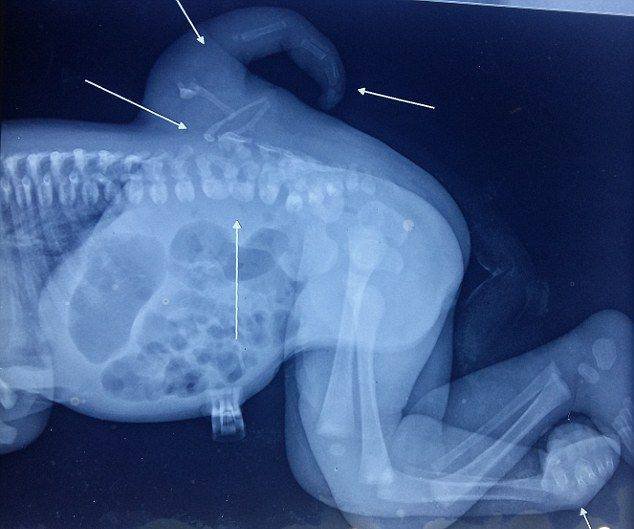

Врачи больницы города Дели пришли на помощь маленькой индианке Варши, страдавшей от полимелии или развития лишних конечностей. Специалисты успешно провели ампутацию выросшей из спины третьей ноги, и теперь двухлетняя девочка может не стесняться своих сверстников.